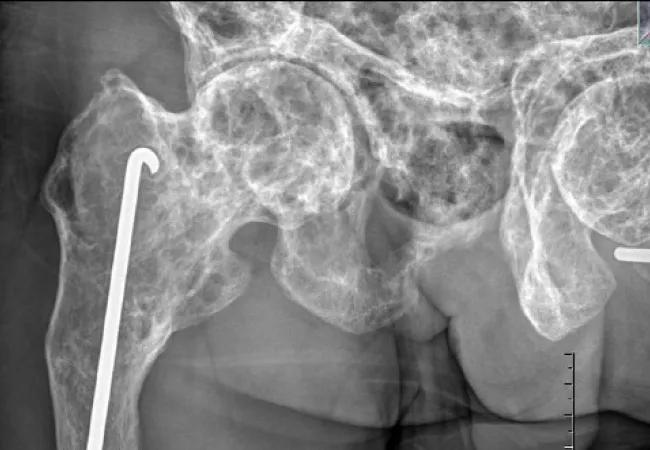

OI refers to a heterogeneous group of connective tissue syndromes stemming from genetic defects that result in an abnormal type I collagen bone matrix. This abnormality typically leads to a heightened risk of fractures over the lifespan (Figures 1 and 2), often with little or no trauma.

Figures 1 and 2. Osteopenia and fractures are the major manifestations of OI, as shown in these fracture images.